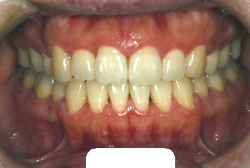

叢生(そうせい)

凸凹な歯並びのことを叢生といいます。矯正歯科に来院する患者様の主訴の中で、最も多いのが「配列の凸凹を真っ直ぐにしたい」というものです。歯の大きさと顎の大きさの調和がとれていないことが原因です。

凸凹を主体としたケースの場合、当院の平均治療期間は18ヶ月ですので、このケースは少し長めに経過しました。理由の一つは凸凹の程度がかなり重症だったと言うことですが、もう一つは、右下第2大臼歯が45度くらい前傾していたため、それを整直化させるために時間を要したと考えています。いずれにしても最終結果は大変よい状態と思います。

治療前は並びが乱れて見た目が悪いというのはもちろん問題ですが、歯科医学的に一番困るのは噛み合わせが悪いという点です。上下の犬歯(3番目の歯)は、上下的に離れた位置にあるため接触することができません。つまり歯としては存在していても、歯としては機能していないということです。